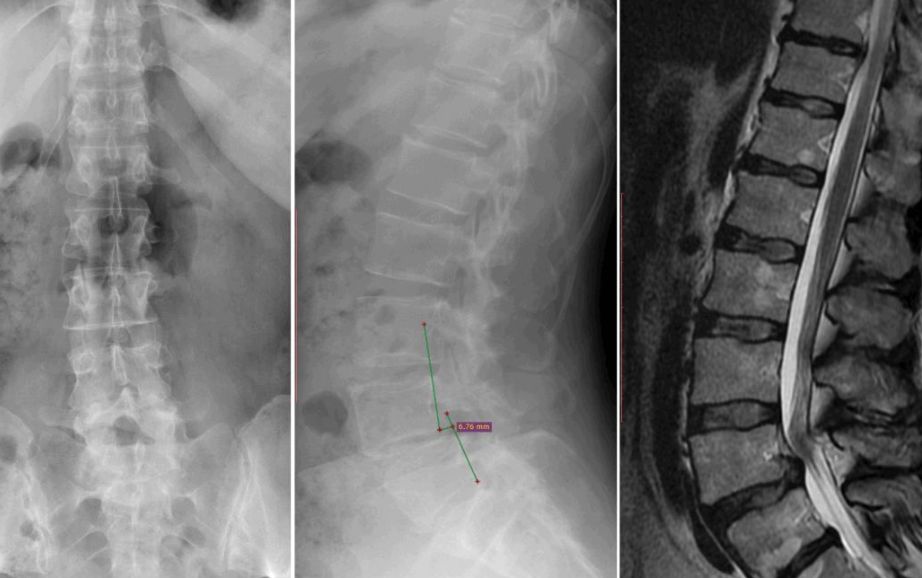

有一种腰痛叫你看着X光片就会觉得腰痛。这就是腰椎滑脱患者的X光片。腰椎滑脱是指腰椎(脊柱)排列正常,而脊柱关节(称为椎间关节)断裂,或椎间盘异常导致脊柱位置偏移。腰椎滑脱由于先天性发育不良、劳损、创伤等原因造成上位椎体与下位椎体位置错位,多见于男性,年龄在20至50岁之间,常发生腰椎滑脱的部位是腰4或腰5。